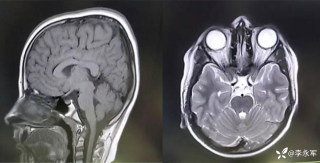

月叔打怪兽急诊科医师

昨天值班遇到的一例晕厥病例,差点漏诊,而最终的解法,始于最简单而质朴的查体。国庆中秋双节的最后一天,8号的早上8点,抢救室床旁晨交班,病人依旧是多而重,交到6床,一个刚入室不久的病人,准备去做CT,夜班医师汇报病史:69岁男性,本次因“头晕伴一过性晕厥1小时”为主诉入抢,1小时前于高铁站因即将赶不上高铁走路快时突发头晕,伴一过性晕厥,约3-4分钟后清醒,清醒后诉今晨未吃早餐,已服用降压药物,仍有头晕头痛、四肢乏力等不适,无胸闷胸痛,无畏寒发热,无咳嗽咳痰,无恶心呕吐,无肢体麻木,无视物模糊等不适,路人拨打120送至我院急诊就诊。既往高血压,长期服用氨氯地平+福辛普利,血压控制一般;糖尿病,长期